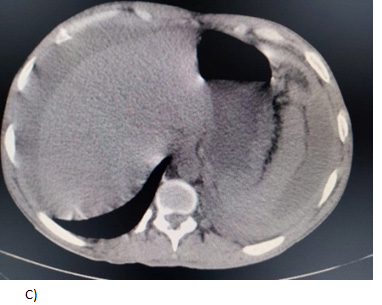

A 27-year-old male with a history of multiple hospitalizations and transfusions for dengue hemorrhagic fever, HIV (+) seven years ago with self-suspended treatment five months ago. He went to the emergency room due to abdominal pain in the epigastrium of three weeks' evolution accompanied by hyporexia, asthenia, and adynamia with hematochezia on one occasion, vomiting coffee grounds on one occasion with respiratory difficulty and dyspnea, denying fever or cough. Physical examination revealed moderate dehydration, pale integuments, tachypnea, and wheezing in the left hemithorax with wheezing in the right hemithorax, abdomen with signs of peritoneal irritation, vital signs: BP 100/60 mmHg, HR 154/min, Breaths 28/min, temp. 36.8 °C. Diagnosis of probable community-acquired pneumonia plus upper gastrointestinal bleeding, severe dehydration and HIV, hypovolemic shock, and septic shock are included. Laboratories: hemoglobin 5.5g/dL, leukocytosis (31000/103/L, absolute neutrophils 28 302/103L, lactic acidosis (PCO2 20.300 mmHg, PO2 73.40mmHg, HCO3 11.50mEq/L and lactate 12.60mmol/L). Tomography with data of honeycombing in both lungs to rule out PTB vs. PCP (Pulmonar tuberculosis vs. Probable Candida parapsilosis), left pleural effusion, bilateral atelectasis, and free peritoneal fluid with suspicion of probable gastric perforation. A CT scan is performed without specifying the origin of the septic shock (Figure 1 & 2). The patient is admitted to the operating room for exploratory laparotomy, purulent fluid (2500ml) is aspirated, a splenic abscess is identified on the diaphragmatic side and splenectomy is performed with the standard technique, admission to the Register Intensive Care Unit, later to the general surgery floor with an in-hospital stay of 9days, he is discharged with control by internal medicine, surgery and SAIH (Hospital Comprehensive Care Services).

Figure 1 Tomography showing a perisplenic collection of heterogeneous density with water and gas density, suggestive of splenic abscess and reactive perihepatic free fluid.